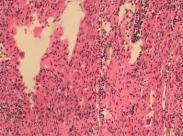

• 朗格漢斯組織細(xì)胞增多癥

628健康網(wǎng)為您分享有關(guān)朗格漢斯組織細(xì)胞增多癥的癥狀,朗格漢斯組織細(xì)胞增多癥的治療方法,朗格漢斯組織細(xì)胞增多癥的預(yù)防...